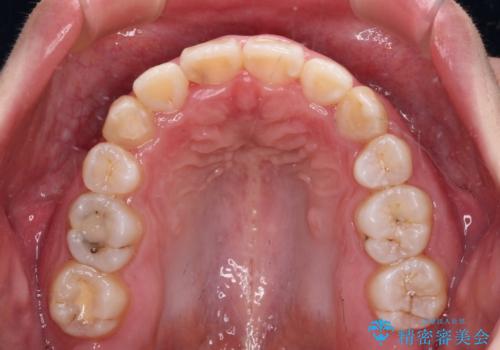

- 上下の八重歯やデコボコを気にして来院された患者様です。

上下ともに八重歯が顕著であったので、上下左右第一小臼歯4本を抜歯し、補助装置を使用して速やかに改善しながら、ワイヤー装置にて矯正治療を行うこととしました。

気になっていた八重歯は装置装着から3か月ほどで解消されました。

2年以内を目標として治療を開始しましたが、1年半ほどで終えることができました。